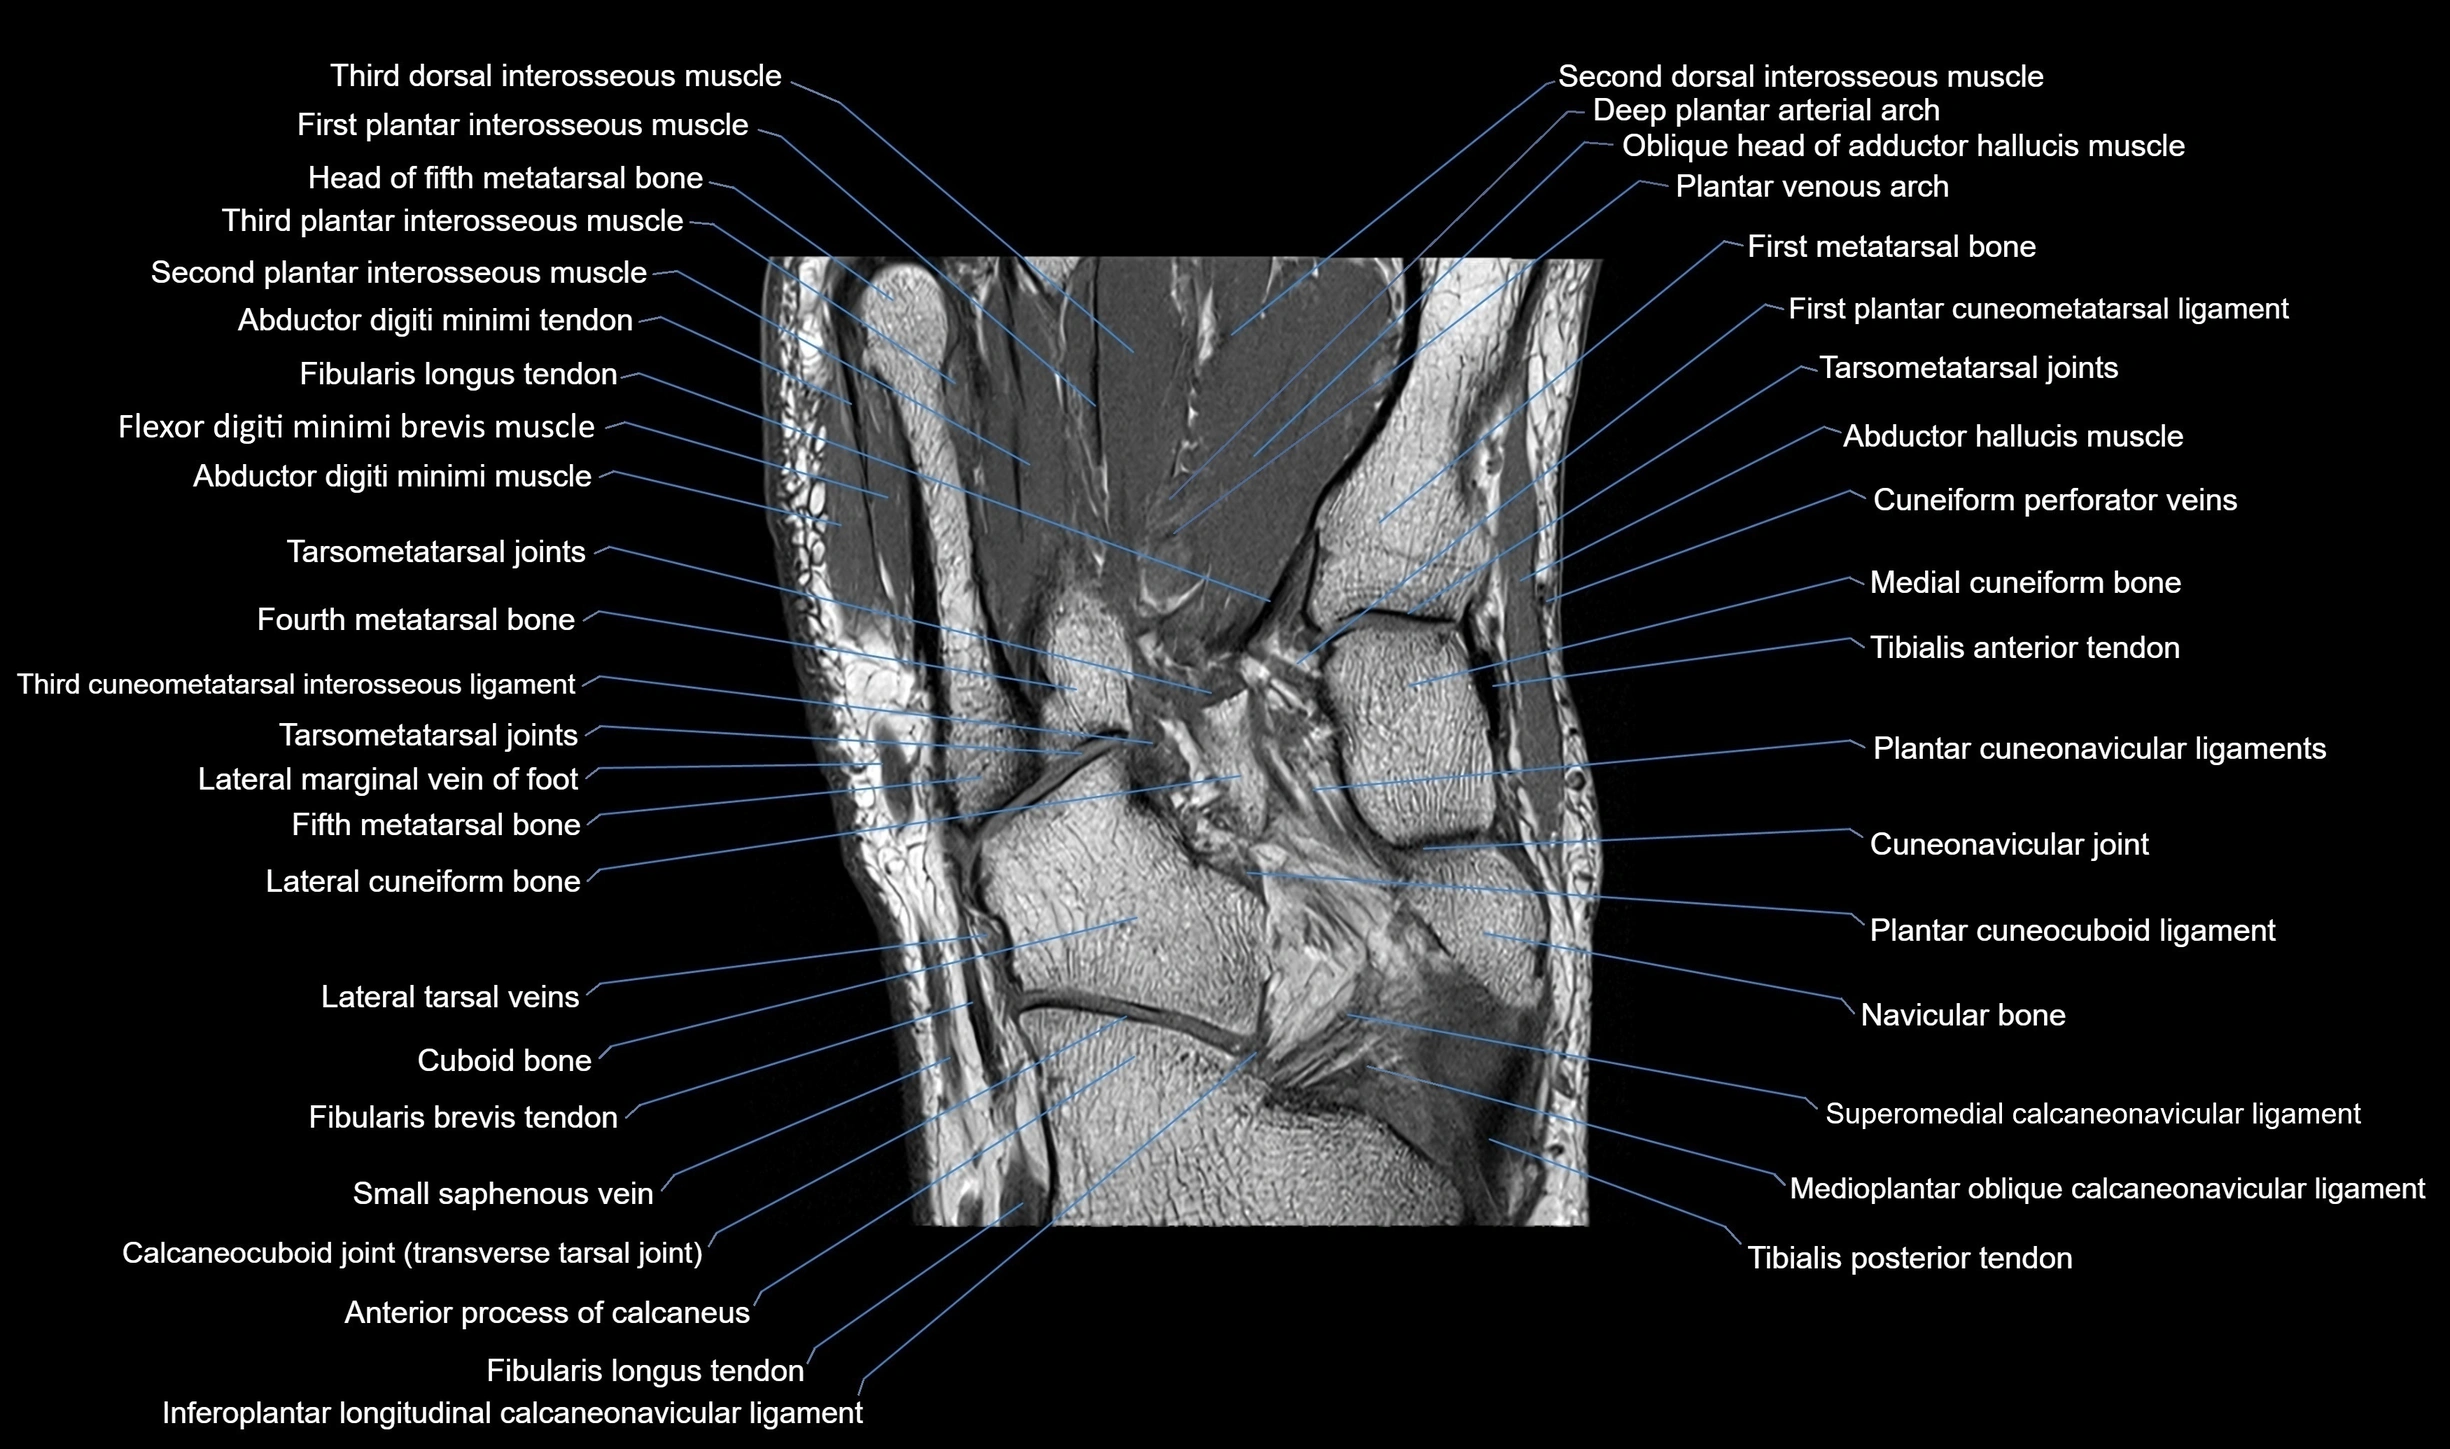

MRI image